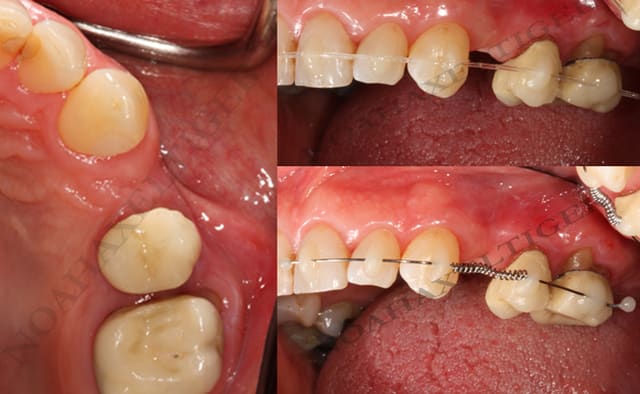

Voici en exemple le cas d’un adulte où la 12 est coincée derrière 11 et 13 etc… (je sais, ploc, j’ai déjà montré il y a quelques temps des photos de ce cas, inutile de me le rappeler gentiment).

14 et 24 sont avulsées.

L’appareillage mis en place est extrêmement simple, des danchamons, le fil NiTi le plus fin qu’on trouve sur le marché (acheté en bobine en « .012 », c’est à dire 0,3mm) et mis en forme avec le manche d’une précelle à la manière d’un bolduc, plus des surélévations molaires en verre-ionomère.

Deux mois plus tard, un élastique très léger est tendu entre les molaires et la canine.

La 13 va-t-elle partir en rotation maximale comme l’affirme le grincheux ?

Le fil utilisé est vraiment très fin. Va-t-il exercer une force suffisante pour vestibuler la 12 en cherchant à reprendre sa forme?

Il y a quelques soucis de nettoyage. Cela va-t-il entraîner des problèmes paro abominables ?

Ci-dessous, photos au départ, le jour de la pose et deux mois plus tard.

A suivre…

Daniel